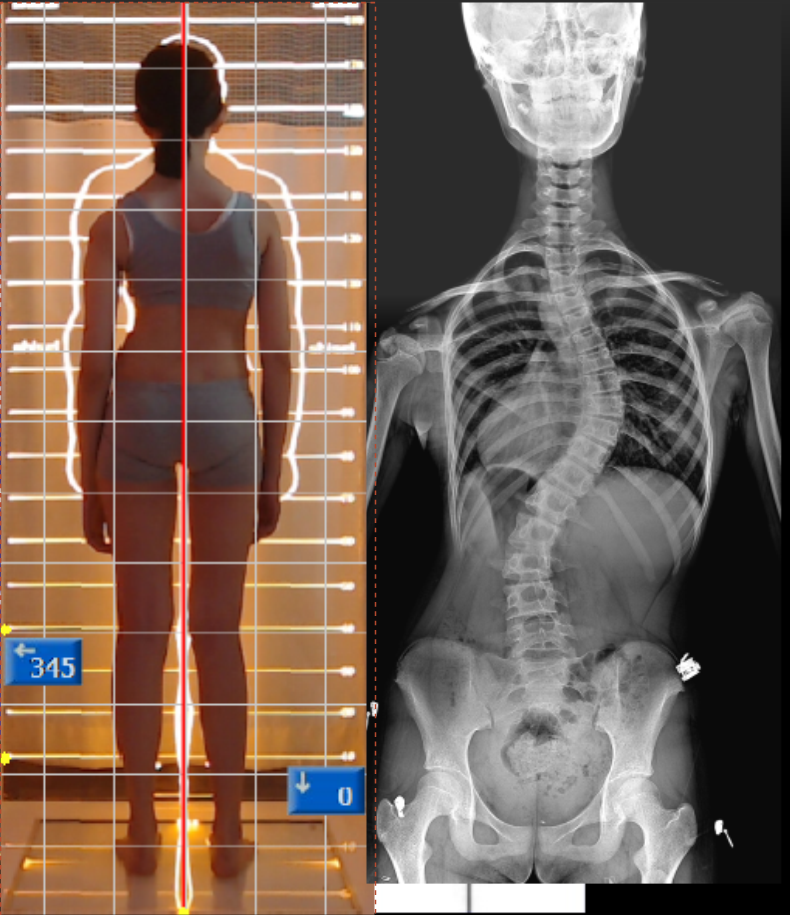

Scoliosis is a three-dimensional (3D) spinal deformity—it

involves not only a side-to-side curve, but also rotation and changes in the

natural front-to-back curves of the spine.

Because of this 3D component, scoliosis can affect posture, breathing

mechanics, muscle balance, and how the body distributes load during standing

and walking.